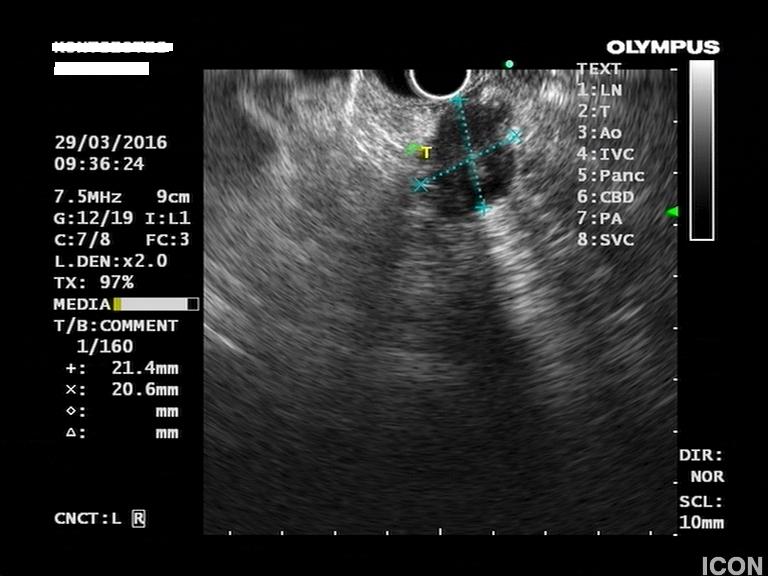

Ο ασθενής υποβλήθηκε σε ενδοσκοπικό υπέρηχο που έδειξε μια υποηχοϊκή μάζα διαμέτρου 21 χιλιοστών, με σαφή όρια, στην παγκρεατική κεφαλή και μεγάλη διάταση του χοληδόχου πόρου και του παγκρεατικού πόρου (διάμετρος 12 χιλιοστά).

Η μάζα είχε ξεκάθαρο διαχωριστικό όριο λίπους από την άνω μεσεντέριο φλέβα και δεν διηθούσε κανένα άλλο μεγάλο αγγείο της περιοχής (πυλαία φλέβα, σπληνοπυλαία συμβολή και αρτηρίες). Έγινε βιοψία με λεπτή βελόνη (FNA Χ3) και το κυτταρολογικό υλικό ήταν θετικό για αδενοκαρκίνωμα παγκρέατος. Το νεόπλασμα κρίθηκε χειρουργήσιμο και ο ασθενής υποβλήθηκε σε επέμβαση Whipple κατά την οποία αφαιρέθηκε πλήρως η παγκρεατική κεφαλή και ο όγκος σε υγιή όρια αλλά και 12 λεμφαδένες που ήταν όλοι αρνητικοί για κακοήθεια. Ο ασθενής υποβάλλεται σε συμπληρωματική χημειοθεραπεία.

Μάζα σώματος παγκρέατος στον ενδοσκοπικό υπέρηχο